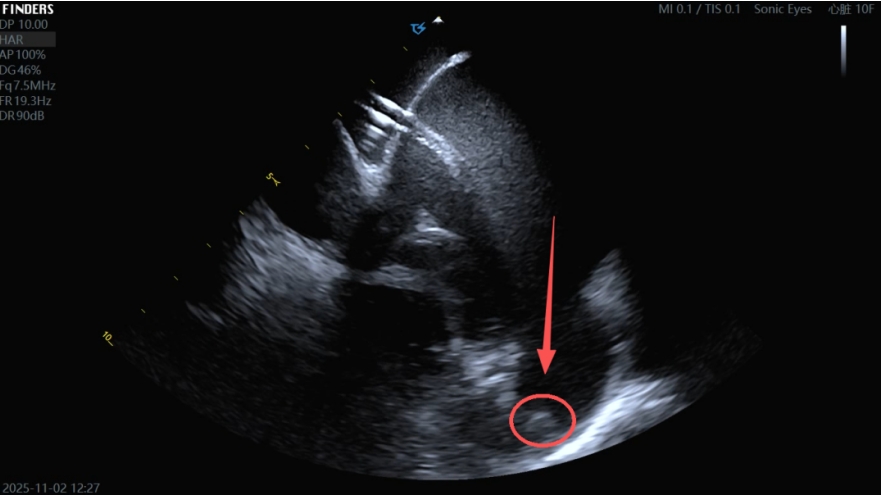

▲超声提示患者左心耳内血栓形成

手术在局部麻醉下进行,团队在DSA及心腔内超声(ICE)引导下精准穿刺房间隔,清晰探查到左心耳内10mm×6mm的团状血栓。

▲左心耳血栓